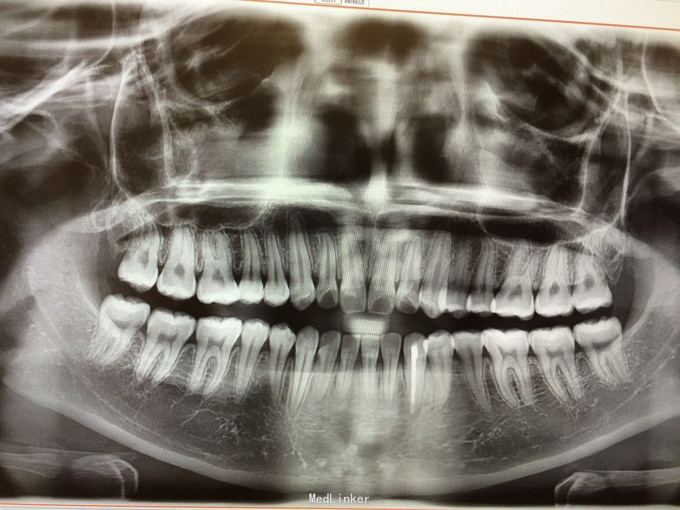

D3牙脱位 D3体外根管治疗后垫底充填,盐水和双氧水浸泡后,刮尽牙根的牙周膜后放置盐水和庆大霉素液中15分钟。局麻下刮除牙槽窝内血凝块至流鲜血后盐水和庆大霉素交替冲洗,明胶海绵拭干牙槽窝,浸泡好的牙体植入牙槽窝内并复位,舌侧树脂牙周夹板固定D123456,牙周上派丽奥。随诊

1天后复诊,3天后复诊,7天后复诊,一个月后复诊,3个月后复诊。1个半月后复诊未发现牙周有较大吸收和炎症感染。